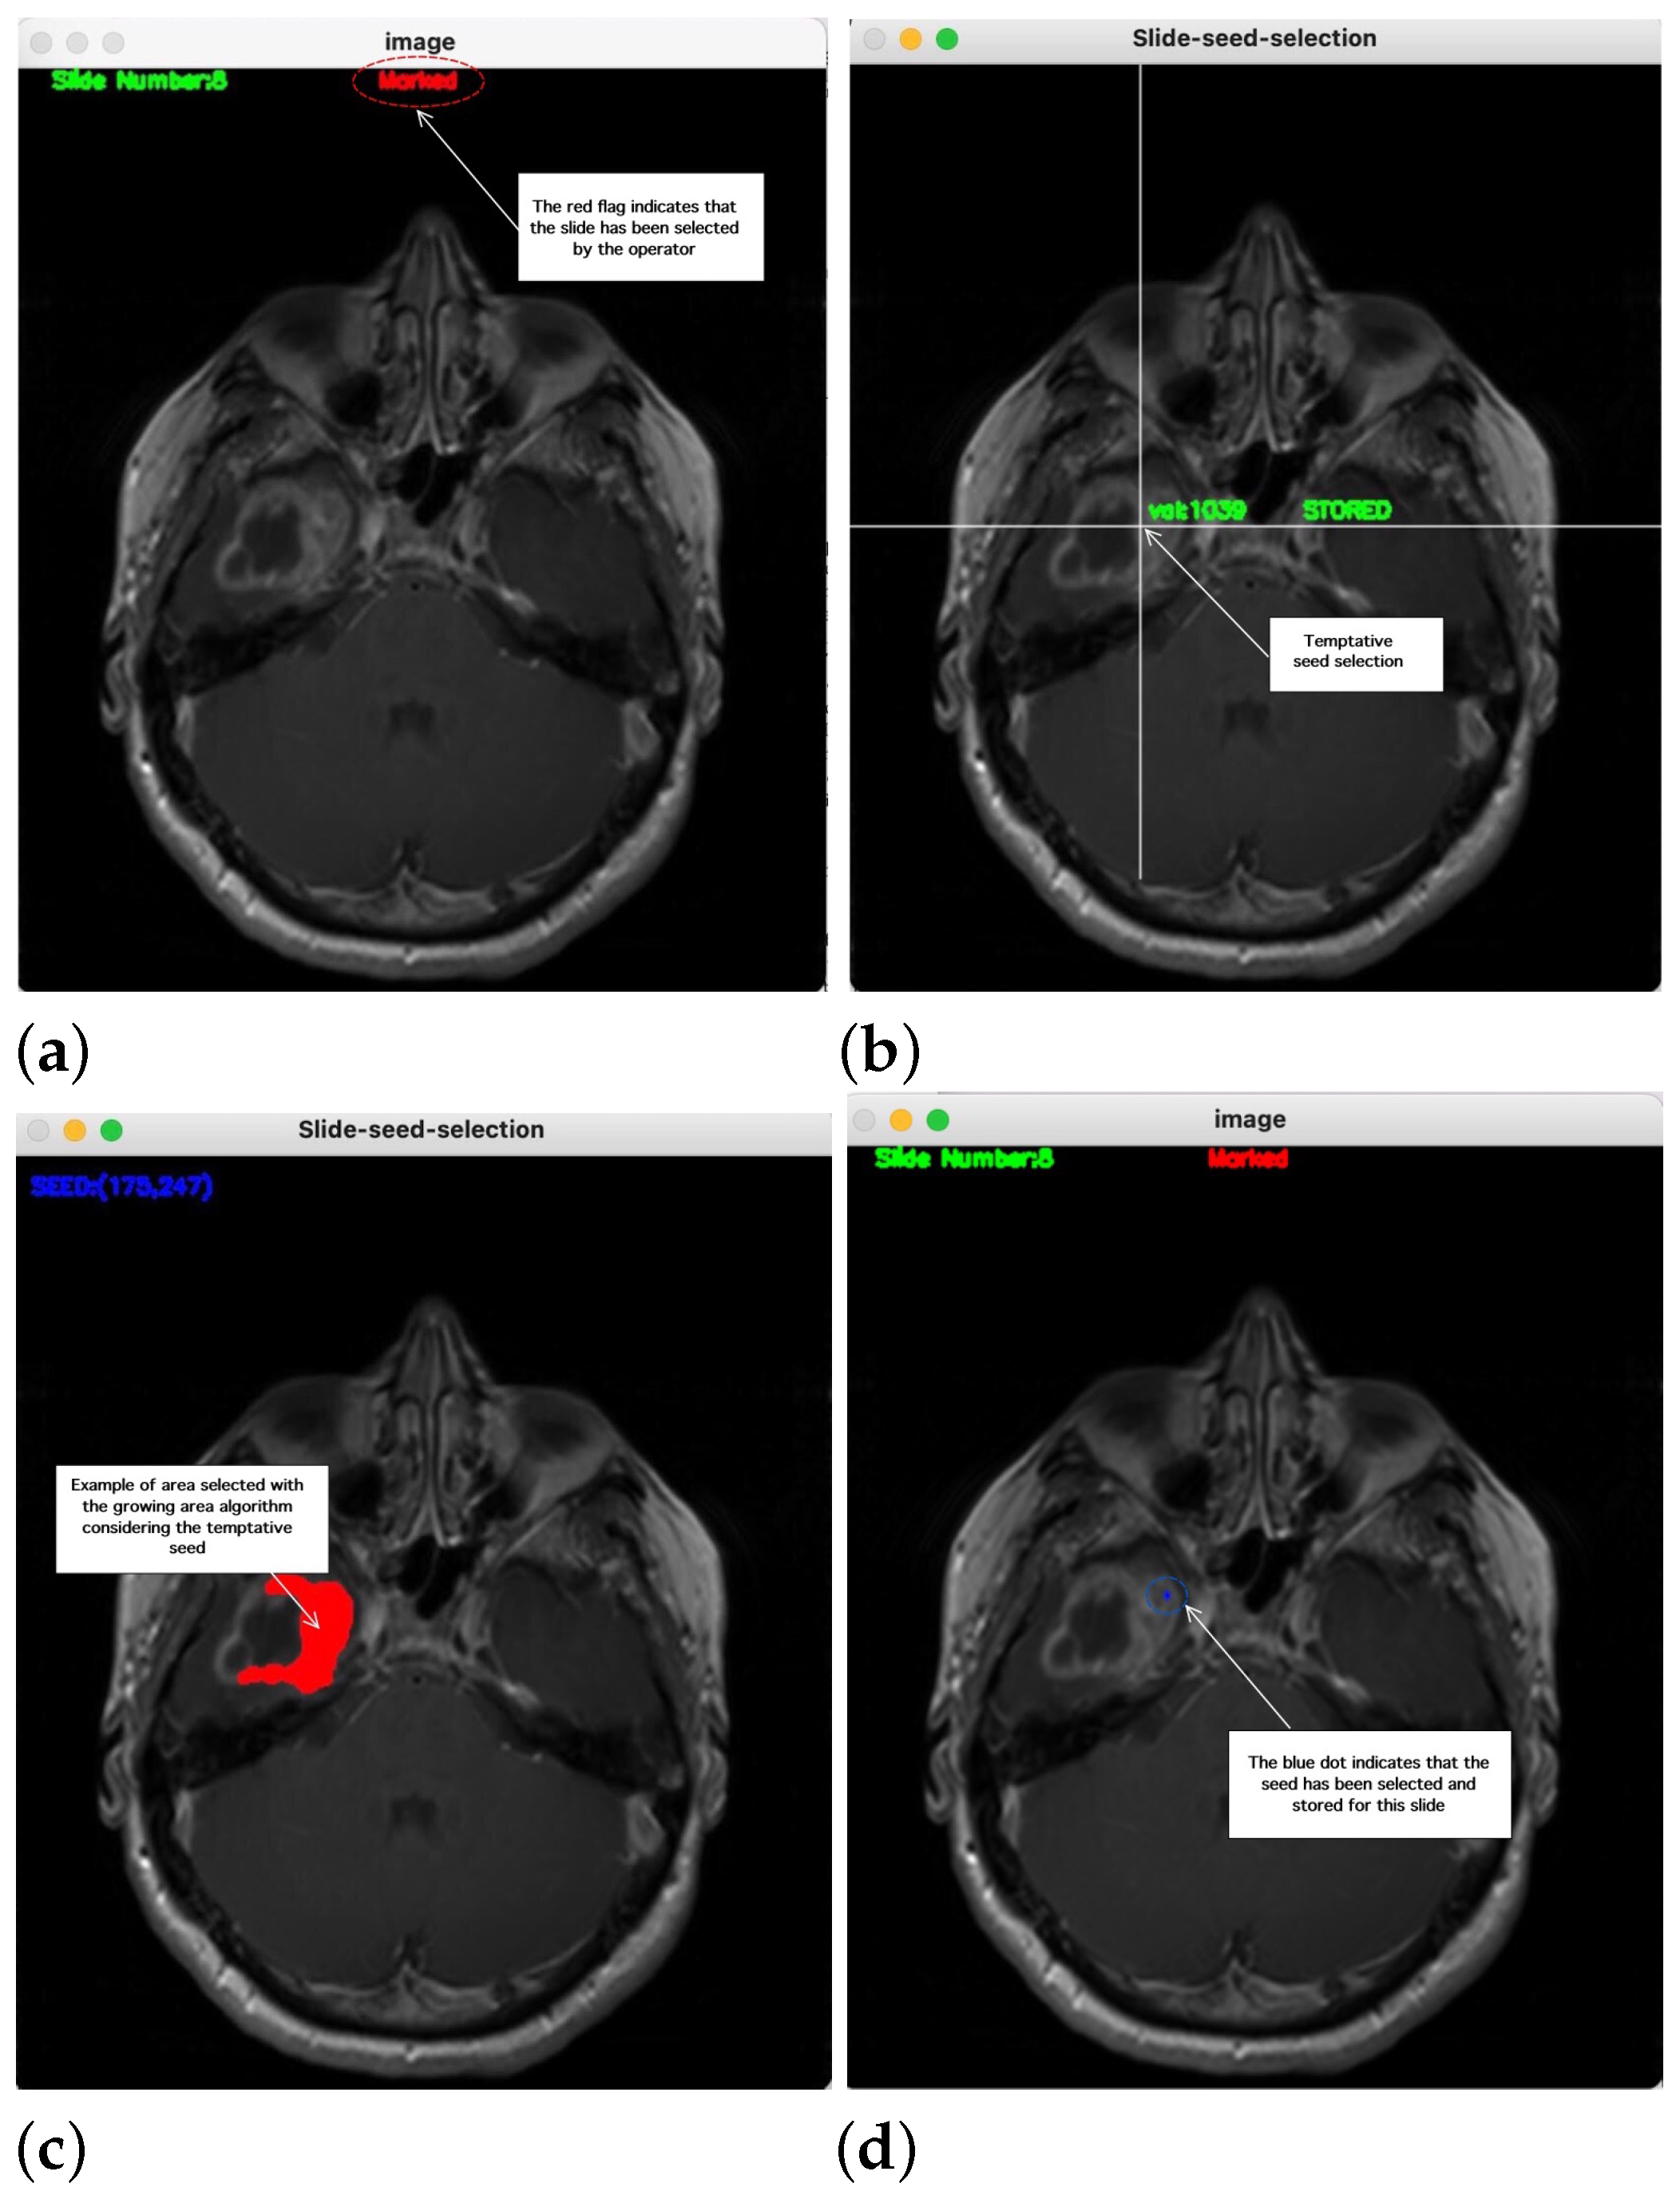

2. Method Description